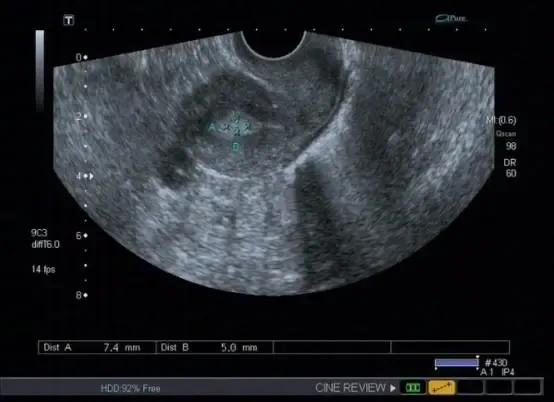

子宫内膜息肉导致宫腔线消失或变形,宫腔内见中-高回声结构,可单发或多个,大小差别很大,常成蛇形,带形或椭圆形。基底部子宫内膜连续可与黏膜下子宫肌瘤鉴别。结节边界清晰,可位于颈管内或宫颈外口。息肉较大时,内膜线显示不清。与子宫内膜癌不易鉴别。 彩色血流显示:中等高阻力的动脉血流或低速的静脉血流信 。 4.子宫内膜息肉病情需要日常监测哪些指标?

标记处息肉